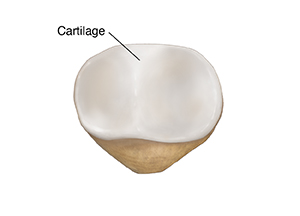

A closer view of the kneecap shows the difference between the smooth cartilage and the rougher bone beneath.

From the back, you can see cartilage. This is tough, cushiony tissue that covers the bone. It helps the kneecap slide easily against the thighbone.

| Back view. |